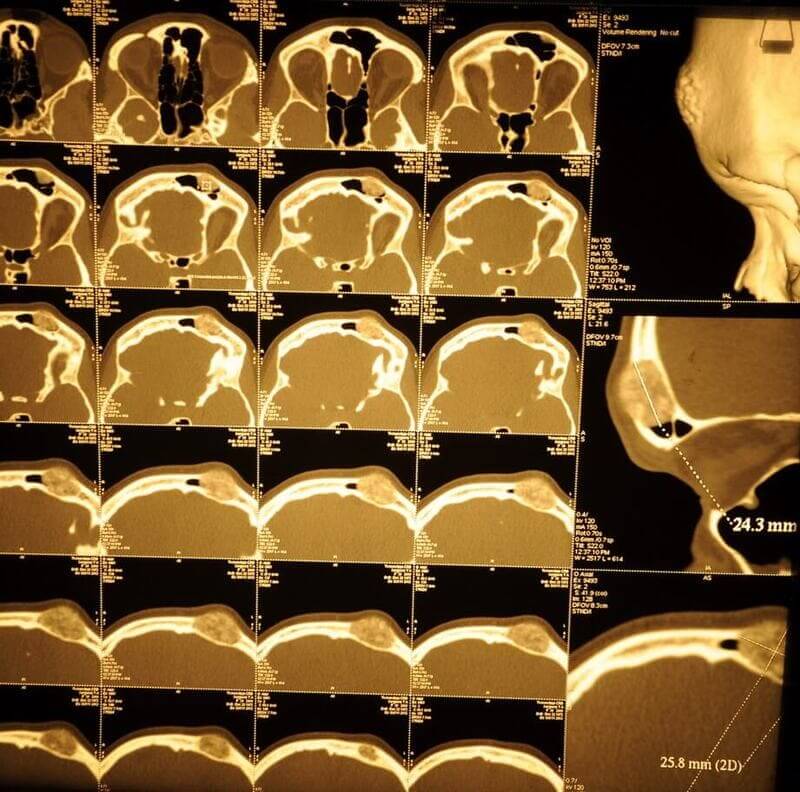

У пациентки выявлена редкая разновидность остеомы - губчатая форма с обширным распространением на лобную кость. Принято решение о косметическом бикоронарном и остеопластическом доступе на лобной кости и лобной пазухе. Разрез спрятан в волосах. Опухоль удалена до твердой мозговой оболочки с , и с местом прорастания в лобную пазуху. Дефект закрыт расщепленным костным аутотрансплантатом с теменной области. Послеоперационное фото сделано на 7 сутки. Отсутствие отеков, гематом, быстрая реабилитация- особенность данной методики.